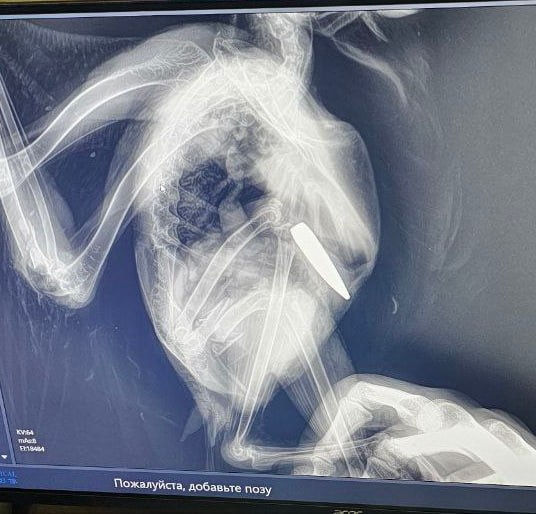

Рентген выявил, что в бок сове попала натовская пуля калибра 5,56. Птице повезло: будь скорость пули больше, пернатую было бы уже не спасти. Однако по воле случая снаряд вошел в тело лишь наполовину. Сова отделалась переломом крыла и бедра. Пулю вытащили. Теперь пернатой предстоит операция в клинике Петербурга. Потом птица обретет новый дом и заботливые руки, рассказали во вторник, 11 марта, в фонде "Защитники Отечества".